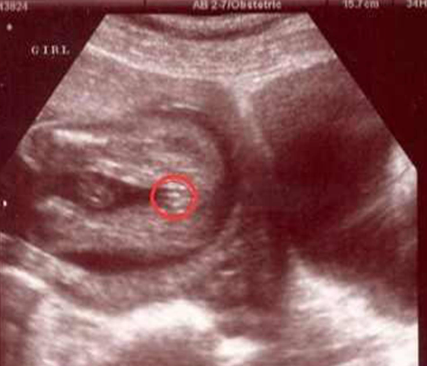

误判的概率还是比较大的。这是因为在检查过程中会受到胎儿姿势、胎儿发育以及操作者经验进而使得结果存在一定的误差性,导致无法准确看出胎儿是男孩还是女孩。B超是一种常用的医学影像检查方法,通常用于检查胎儿的发育情况,虽然也能够用于鉴定胎儿**,但结果一般不是很准,所以夫妻不要对这项检查结果太过于相信。

在怀孕之后,胎儿的生殖器官也会逐渐发育成熟,因此能够通过一些方式来检测出胎儿的性别,B超是产检中必不可少的一项检查,但通过这个方式来看男女的误差性会很大,主要是和检查时胎儿的姿势、胎儿发育以及操作的准确性有很大的关系,即使是找熟人做的B超,结果也只能作为一个参考,该做的检查也要按时做。

1.胎儿姿势:胎儿在子宫内的姿势可能会影响B超图像的清晰度,从而影响性别的观察和判断。不过,4个月的胎儿并不能够配合翻身,因此结果会因此出现一定误差。

2.胎儿发育:在早期的胎儿发育阶段,性别鉴定的准确性可能会受到影响,因为男女生殖器官的发育在早期可能并不明显,也有可能因为着床时间晚从而导致该器官发育不成熟。

3.操作者经验:B超操作者的经验和技术水平也会对性别鉴定的准确性产生影响,一般经验丰富的医生通过这种方式俩查看结果误判的可能会更小。